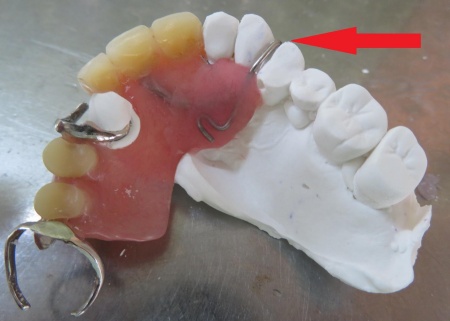

続いて、左上の前から4番目の歯に合わせて金属ワイヤーを成形し、新しいクラスプを作製します。

歯の形にぴったり沿うよう細かく調整し、入れ歯をしっかり支えられる強さに仕上げました。

治療中画像 治療中画像 治療中画像 治療中画像